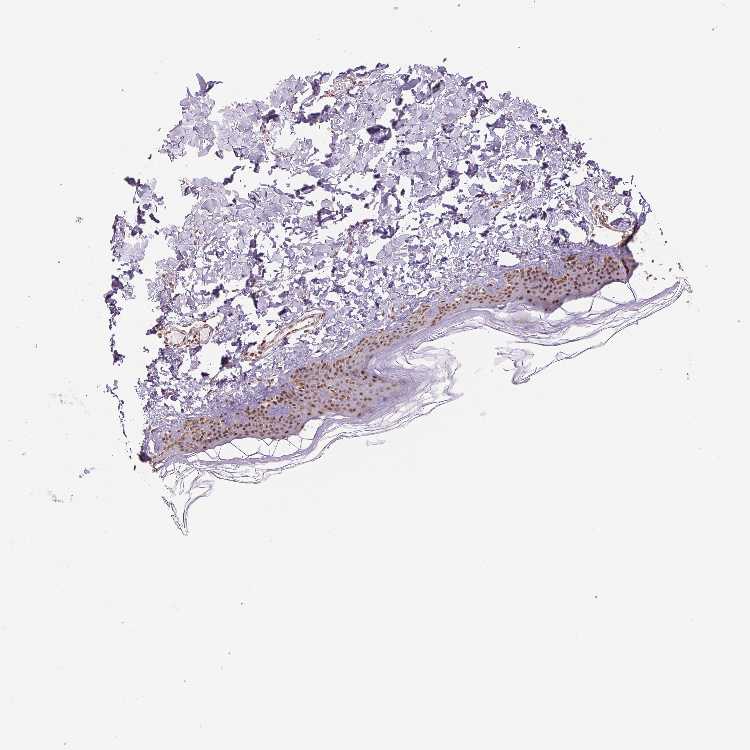

SKIN 1 - Antibody stainingi

Antibody staining in the annotated cell types in the current human tissue is reported as not detected, low, medium, or high, based on conventional immunohistochemistry profiling in selected tissues. This score is based on the combination of the staining intensity and fraction of stained cells.

Each image is clickable and will lead to virtual microscopy that enables deeper exploration of all samples and also displays staining intensity scores, fraction scores and subcellular localization as well as patient and tissue information for each sample.

Antibody HPA062997Antibody CAB014874

Langerhans HighHigh

Fibroblasts HighHigh

Keratinocytes HighHigh

Melanocytes HighHigh

SKIN 2 - Antibody stainingi

Epidermal cells HighHigh